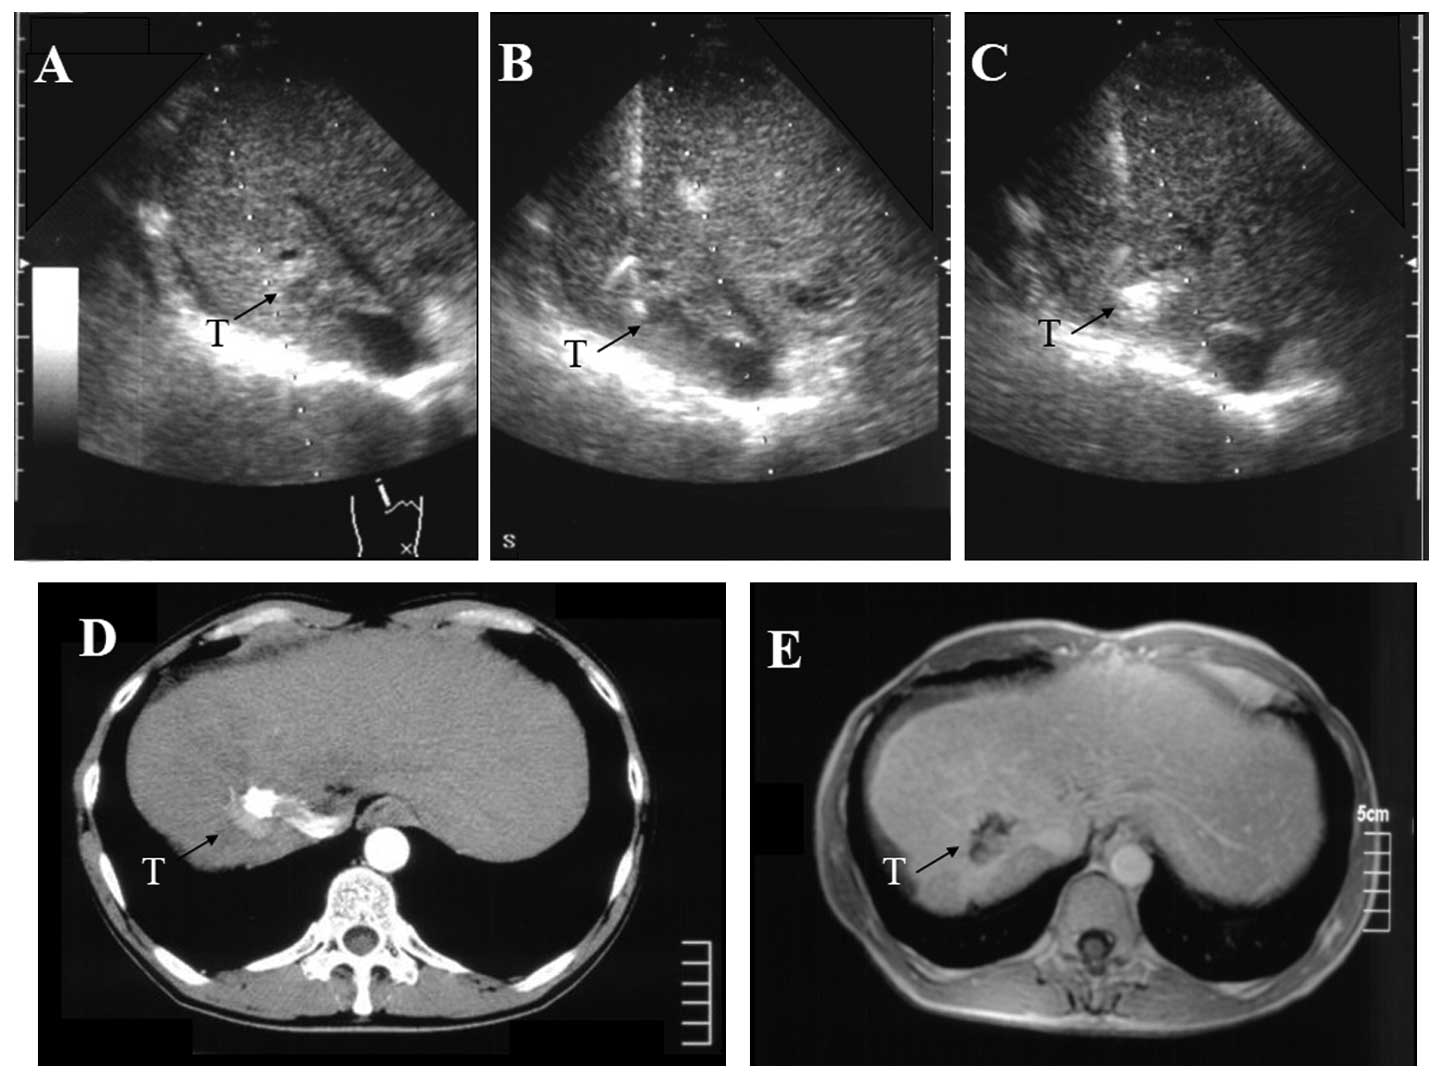

Ethanol injection therapy for small hepatocellular carcinomas located beneath a large vessel using a curved percutaneous ethanol injection therapy needle

Percutaneous ethanol injection therapy (PEIT) has been administered as a safe therapeutic modality for patients with small hepatocellular carcinoma (HCC). Due to the nature of the straight approaching line of a PEIT or radiofrequency ablation needle, penetrating the vessels that are interposed between the dermal insertion point and the nodule is unavoidable. A device with an overcoat needle and coaxial curved PEIT needle was created that facilitated a detour around interposing large vessels in order to avoid unnecessary harmful effects that result from the PEIT procedure. Two cases of HCC located adjacent to a neighboring large vessel were treated with a curved PEIT needle. The curved PEIT needle, which is connected to an outer needle, enabled deviation around the interposing vessels and successful connection with the HCC. Careful use of the curved line of the PEIT needle enabled the safe and successful performance of the PEIT without any requirement for specific training. This hand‑assisted technique may be an applicable treatment for small HCC located beneath large vessels as a direct therapeutic method using ultrasound guidance.

Figure 1